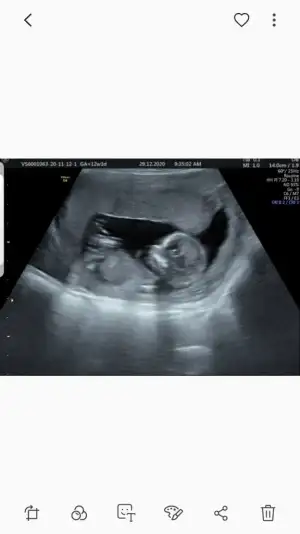

dr soylemeden siz gorun genital nub teorisi ( bebegin cinsiyeti)

Merhaba tekrar yükledimm ama bakabilir misiniz :)

• Screenshot_20210112-230651_WhatsApp.webp

Screenshot_20210112-230651_WhatsApp.webp

7,5 KB · Görüntüleme: 53